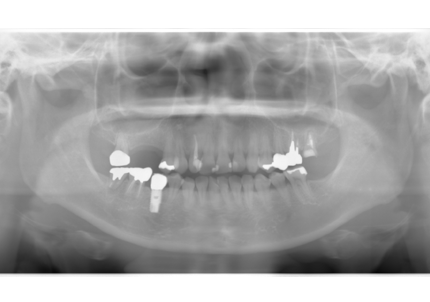

1.初診時(2015年6月)

2.最終補填物装着(2018年3月)

3.術後8年経過(2023年3月)

術後8年経過良好

2015年6月初診時レントゲン

2023年3月レントゲン 経過良好